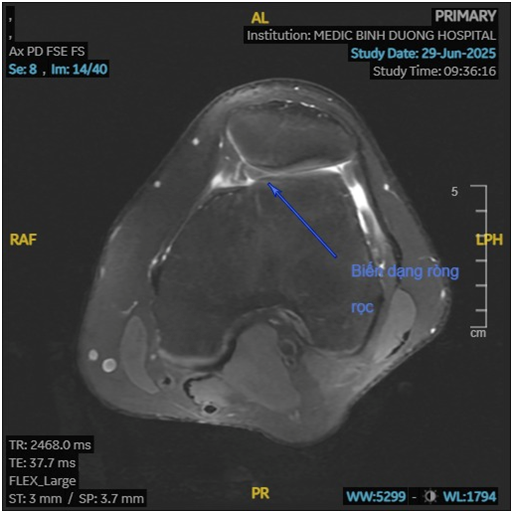

Hình 2. Ròng rọc xương đùi biến dạng do loạn sản

Loạn sản ròng rọc xương đùi (Trochlear Dysplasia) là một dị tật bẩm sinh hiếm gặp của khớp gối, đặc trưng bởi sự phát triển bất thường của rãnh ròng rọc, tức là phần lõm ở xương đùi nơi xương bánh chè trượt lên xuống khi gập hoặc duỗi gối.

Ở người bình thường, rãnh ròng rọc có hình chữ V, sâu và đối xứng, giúp định hướng và giữ xương bánh chè trượt đúng hướng khi gập duỗi khớp gối. Tuy nhiên, khi bị loạn sản:

- Rãnh trở nên quá nông hoặc thậm chí phẳng

- Gây mất ổn định cho xương bánh chè

- Dễ dẫn đến trật khớp bánh chè tái phát, đau, và thoái hóa khớp sớm

Ở khớp gối, ròng rọc xương đùi đóng vai trò là “đường ray”, còn xương bánh chè là “bánh xe” di chuyển. Khi đường ray bị biến dạng (quá nông hoặc lệch trục), “bánh xe” sẽ dễ trượt khỏi đường, gây ra hiện tượng trật khớp bánh chè.

3. Chụp cộng hưởng từ (MRI)

- MRI giúp đánh giá rõ hơn:

- Hình thể rãnh ròng rọc

- Tổn thương dây chằng, sụn, sụn chêm

- Mức độ viêm, tràn dịch khớp